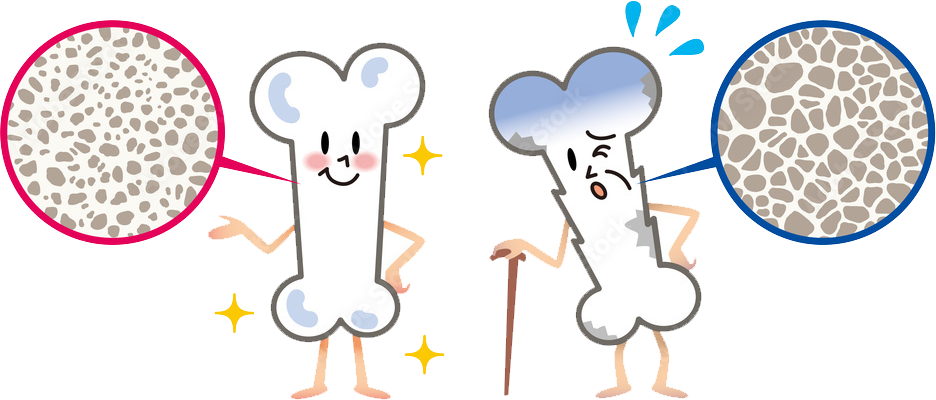

骨粗しょう症による骨折は、強い衝撃だけでなく気づかぬうちに起こることもあります。

骨粗しょう症が原因で知らないうちに背骨が折れる“いつのまにか骨折”もあり、放置すると慢性的な腰痛や足の力の低下につながります。